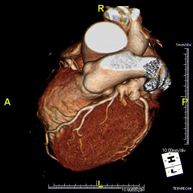

- Angio-TC Cardíaco o TC Cardíaco

El angio-TC Cardíaco o Coronariografía no invasiva es una prueba diagnóstica que consiste en el estudio de las arterias del corazón o arterias coronarias mediante el empleo de un equipo de TC Multidetector de última generación y de un contraste yodado, obteniendo imágenes bi y tridimensionales. El TC Multidetector o TCMD permite una adquisición de imágenes tan rápida, que se pueden valorar las arterias coronarias con una alta precisión anatómica: estrechamientos o estenosis, calcificaciones, variantes anatómicas, etc., ya que gracias a su rapidez evita el artefacto que provoca el movimiento constante del corazón (tarda menos de diez segundos en adquirir unas 1000 imágenes). La información obtenida precisa de un tratamiento en estaciones de trabajo con programas especializados en la reconstrucción de las arterias coronarias que permiten valorar el número, la localización y las características de las lesiones. Toda esta información se obtiene de manera no invasiva: solo se requiere la punción de una vena periférica (en el brazo). Es necesario que la frecuencia cardíaca no supere los 75 latidos por minuto, por lo que algunos pacientes deberán realizar un tratamiento previo con un fármaco betabloqueante.

- Angio-TC Cardíaco

El angioTC Cardíaco o Coronariografía no invasiva es una prueba diagnóstica que consiste en el estudio de las arterias del corazón o arterias coronarias mediante el empleo de un equipo de TC Multidetector de última generación (64 coronas o filas de detectores) y de contraste yodado, obteniendo imágenes bi y tridimensionales. El TC Multidetector 64 o TCMD64 permite una adquisición de imágenes tan rápida, que se pueden valorar las arterias coronarias con una alta precisión anatómica (estrechamientos o estenosis, calcificaciones, variantes anatómicas, etc.), ya que, gracias a su rapidez, evita el artefacto que provoca el movimiento constante del corazón (tarda menos de diez segundos en adquirir unas 1000 imágenes). La información obtenida precisa de un tratamiento en estaciones de trabajo con programas especializados en la reconstrucción de las arterias coronarias que permiten valorar el número, la localización y las características de las lesiones. Toda esta información se obtiene de manera no invasiva: sólo se requiere la punción de una vena periférica (en el brazo). Es necesario que la frecuencia cardíaca no supere los 75 latidos por minuto, por lo que algunos pacientes deberán realizar un tratamiento previo con un fármaco betabloqueante.